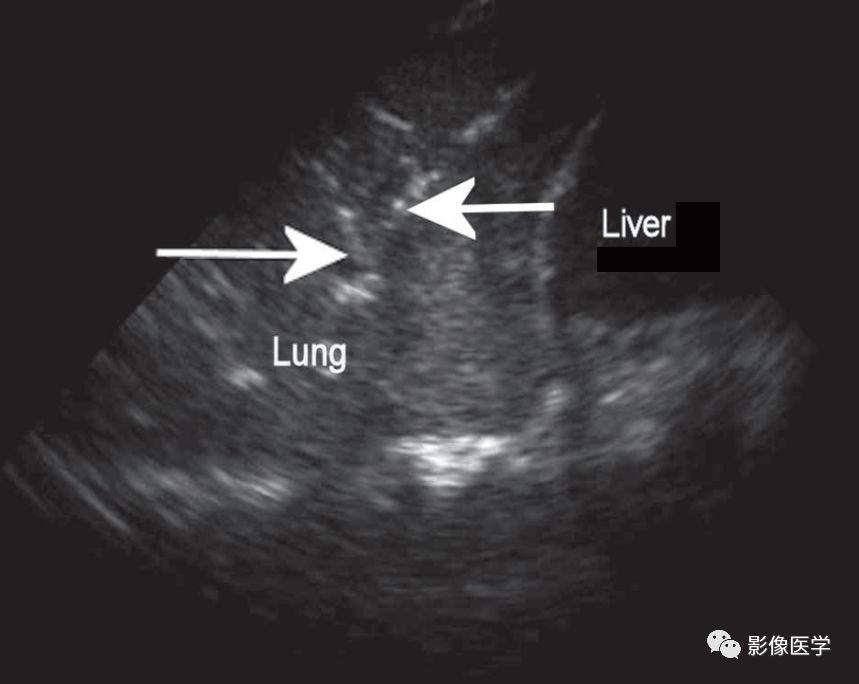

图6-1 肺炎的超声征象

显示肺组织肝样变伴树枝状支气管充气征(箭头)[引自Blaivas M. Lung ultrasound inevaluation of pneumonia. J Ultrasound Med,2012,31(6):823-826]。